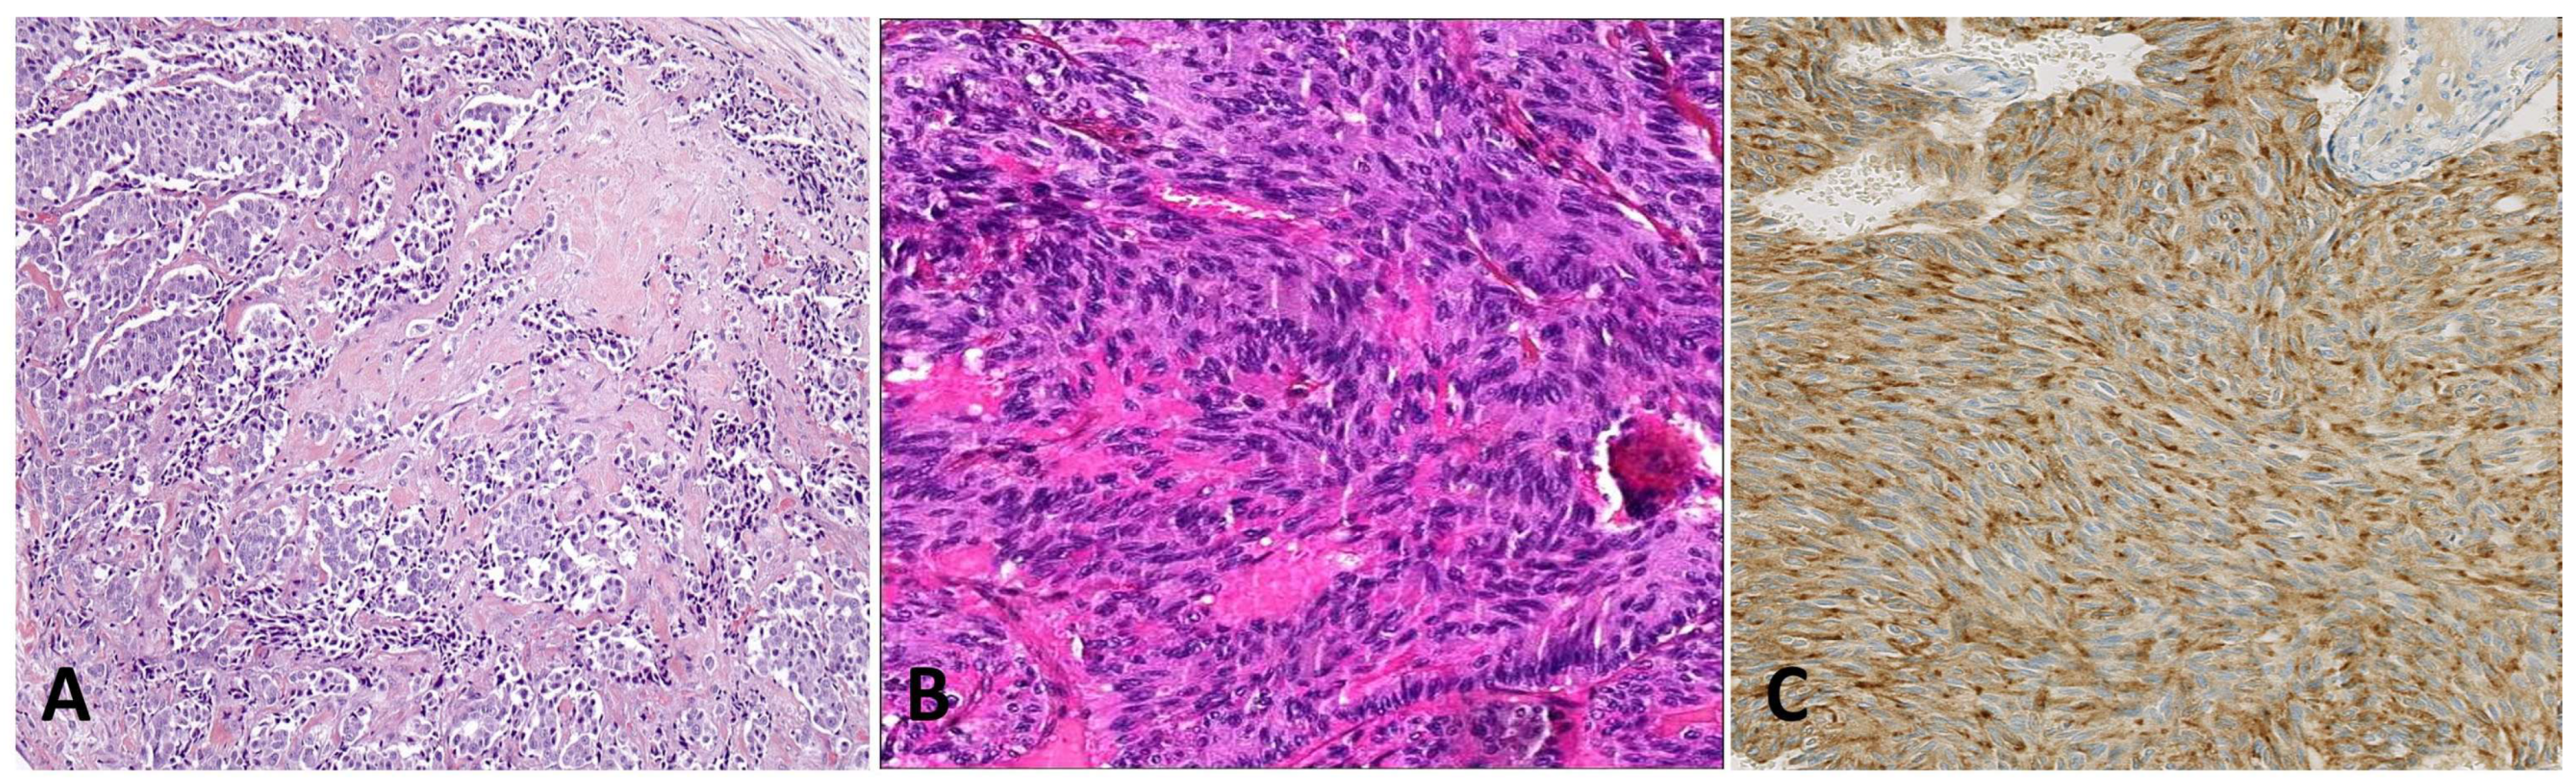

4.7. Leiomyosarcoma